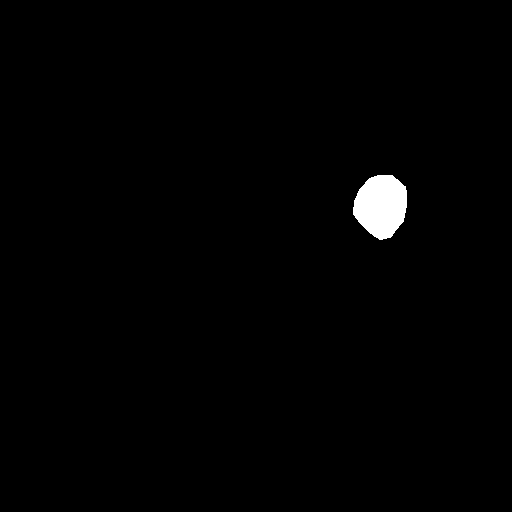

Extensive experiments have been performed in the current setup, and experimental outcomes are reported with the demonstration of numerical and statistical analyses using the proposed QFS-Net, QIS-Net [39], convolutional U-Net [18] and Residual U-Net (URes-Net) architectures [20]. The human expert segmented skull-tripped contrast enhanced DSC brain MR input image slices of size and ROIs are provided in Figure 5 as samples. The demonstration of QFS-Net segmented images followed by the essential post-processed outcome on the slice no. for class level with four distinct activation schemes () are shown in Figure 6. It is evident from the experimental data provided in Table LABEL:tab1 that the proposed QFS-Net performs optimally for the -connected quantum fuzzy pixel information heterogeneity assisted activation () with and gray scale set in comparison with other thresholding schemes and gray scale sets under the four evaluation parameters () [44]. The segmented tumors obtained using the proposed self-supervised procedure under class transition levels with four different thresholding schemes , , and are demonstrated in Figures 7- 8 for the class boundary sets and [39], respectively. The segmented images using the remaining two class boundary sets ( and ) [39] are provided in the supplementary materials section. The segmented ROIs describing the whole tumor region after the masking procedure using QIS-Net, U-Net and URes-Net are also reported in Figure 9.